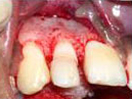

Splinting of Fracture

Fragments with direct

Composite Veneering

Tooth with Fracture Extending Sub-Gingivally

In the process of Removal

of Pulp after access preparation

then Cleaning and Shaping done.